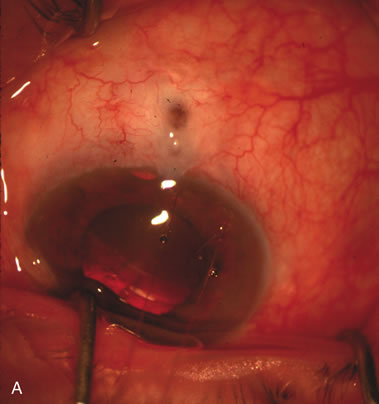

Fig. 1. The anatomic advantage of small incision cataract surgery for the glaucoma patient. A. Long-term bleb function with a large cataract incision is difficult to achieve with either ECCE-trabeculectomy or trabeculectomy followed later by ECCE. This bleb failed to form sufficiently when combined with large incision ECCE. The inflammation, bleeding, and long-term wound healing with stimulation of fibroblasts associated with this technique are more likely to cause bleb failure. In addition, the increased iris manipulation necessary to deliver the nucleus and subsequent iris repair adds to the long-term breakdown of the blood aqueous barrier. B and C. Two-site phacotrabeculectomy has the advantage of small incision cataract surgery combined with separate site trabeculectomy. The incision size is one third the size of the standard ECCE. The inflammation is less severe, and cataract wound healing is confined to the temporal area. Visual rehabilitation with phacoemulsification and foldable IOL is much faster. Phacoemulsification allows successful lens extraction even in the unfriendly environment of a smaller pupil compared with ECCE. The trabeculectomy is performed in an entirely different site, well away from the wound healing associated with temporal phacoemulsification. The likelihood of this filter functioning long-term is greater than with ECCE-trabeculectomy. D. The surgeon also has the option of single-site phacotrabeculectomy with foldable IOL. Both the lens extraction and trabeculectomy are performed through one small 3.5-mm limbal incision.

In years past, patients with both cataract and glaucoma frequently provided overwhelming surgical challenges for the ophthalmologist. The ability to carry out phacoemulsification through a 3.2-mm corneal incision along with inserting a foldable IOL is a vast improvement over 11-mm incisions that were common a decade ago (Fig. 1). The anatomical and inflammatory changes to the eye are less with small incision techniques, improving the likelihood of success with concomitant glaucoma surgery. Pharmacologic inhibition of fibrosis along with postoperative wound revision increases the long-term success rate of filtration surgery when combined with lens extraction. (Fig. 2). The learning curve may be steep at times, but the blending of cataract and glaucoma surgical skills slowly falls into place as the surgeon constantly learns and upgrades his or her technique.